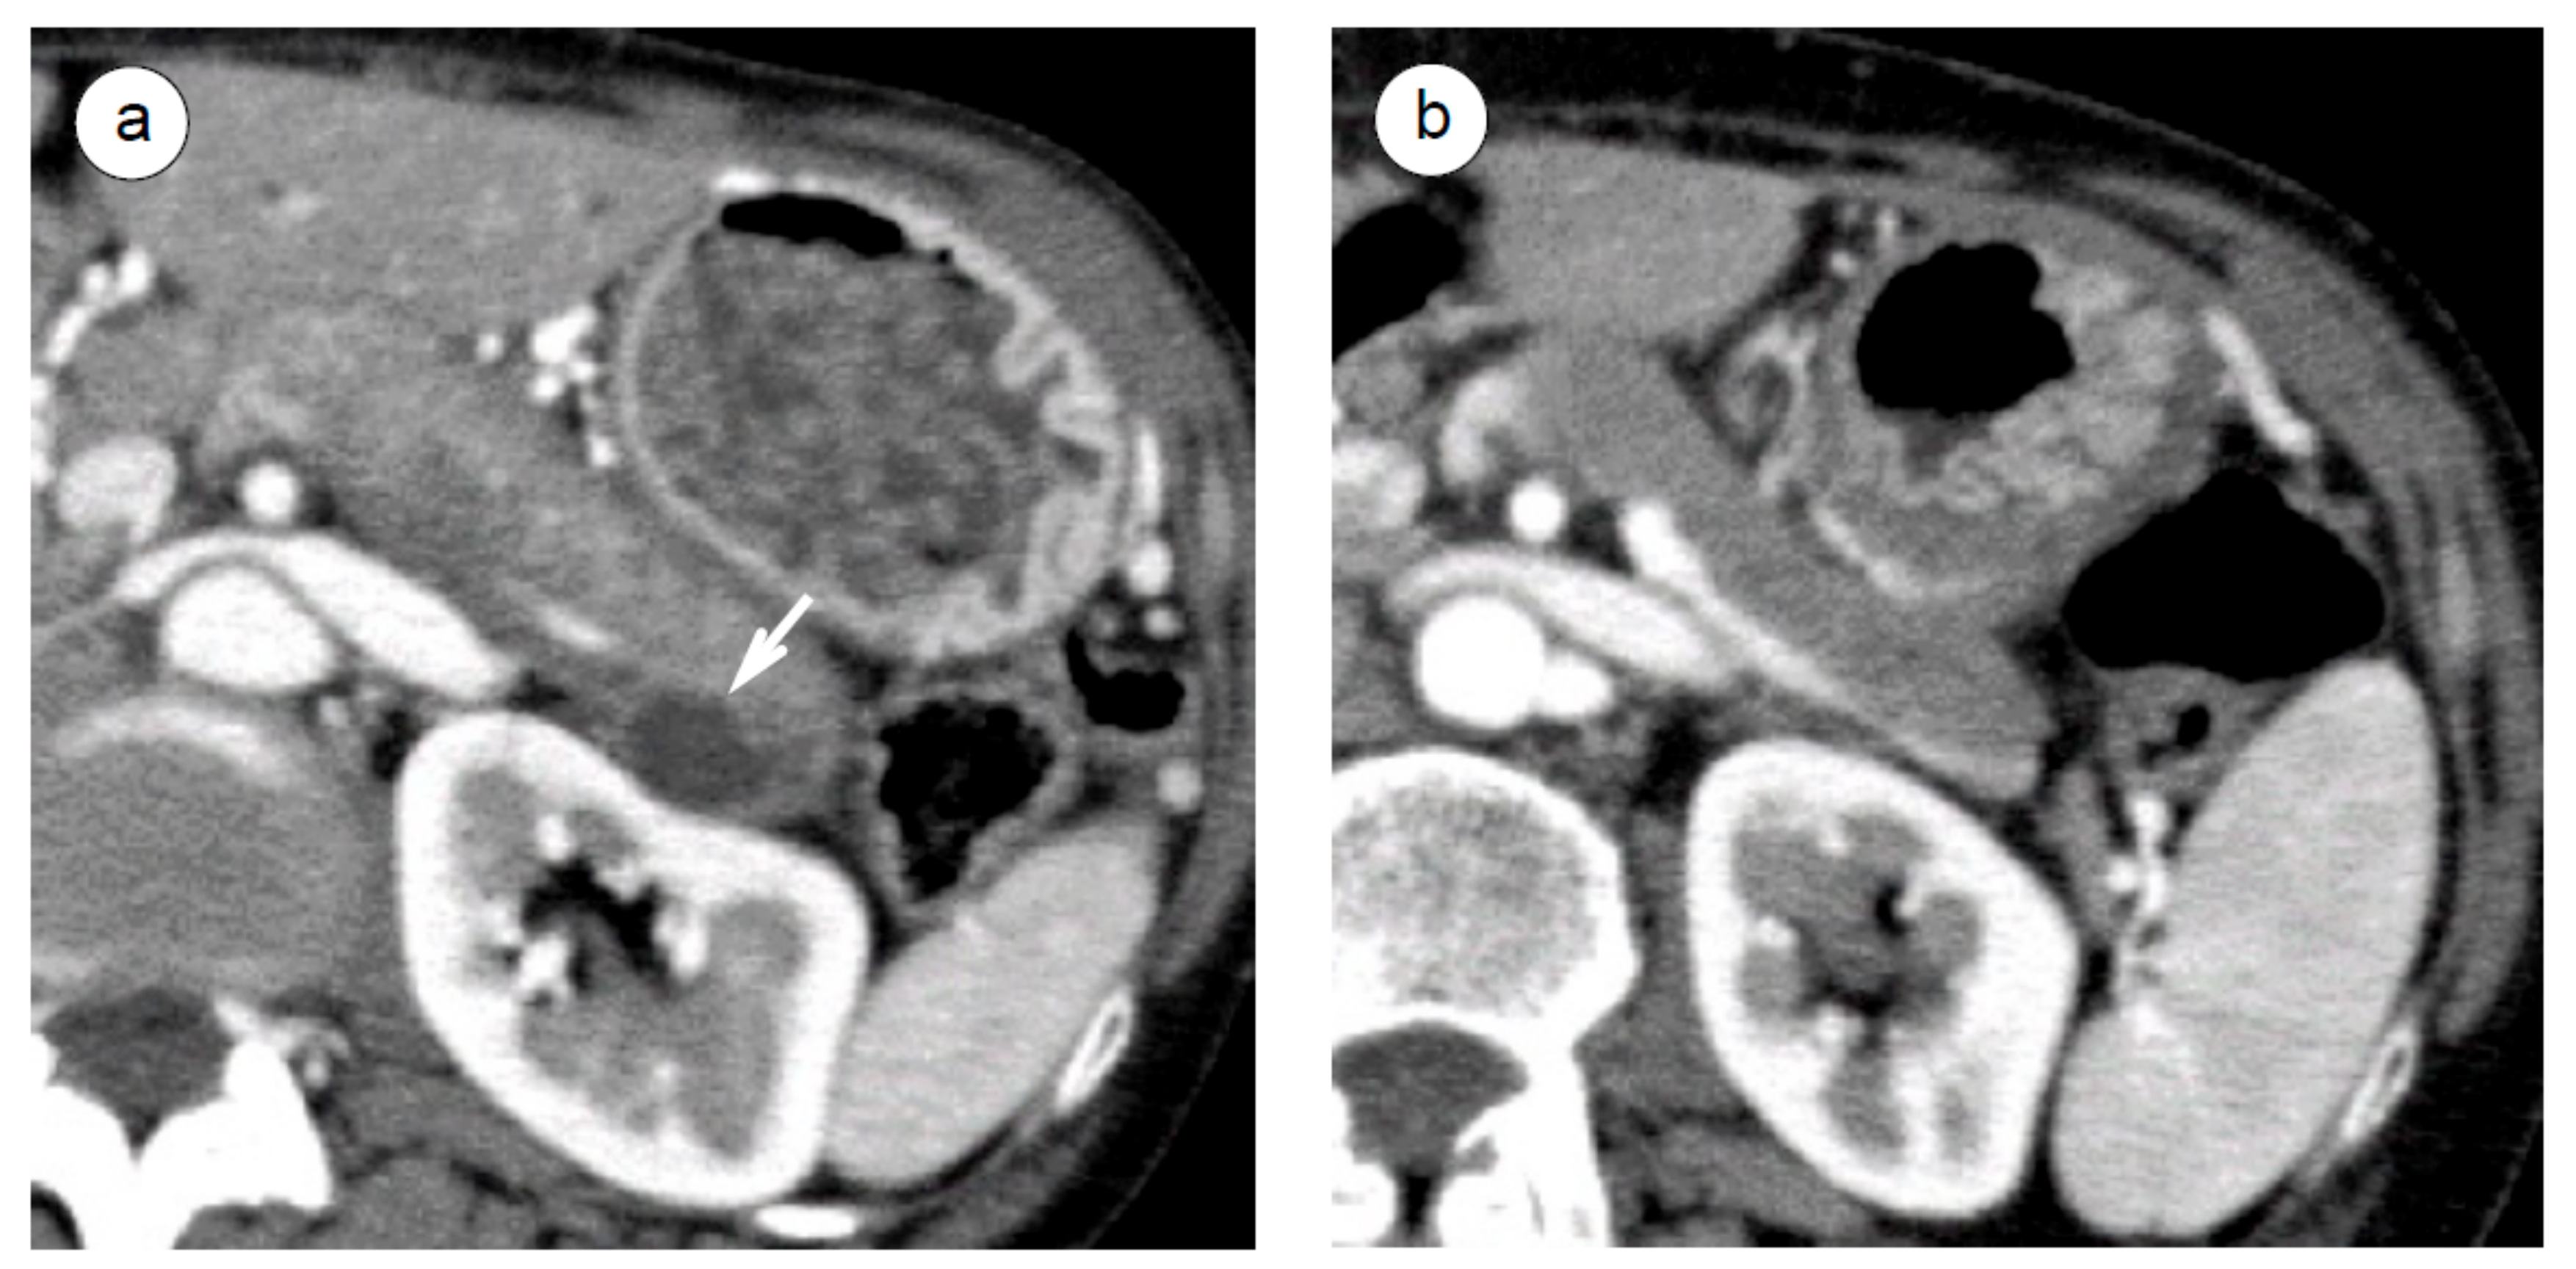

- Matsubayashi, H.; Iwai, T.; Matsui, T.; Wada, T.; Kawata, N.; Ito, H.; Sasaki, K.; Uesaka, K.; Ono, H. Pancreatic cystic lesions with atypical steroid response should be carefully managed in cases of autoimmune pancreatitis. J. Gastroenterol. Hepatol. 2016, 31, 270–276. [Google Scholar] [CrossRef]